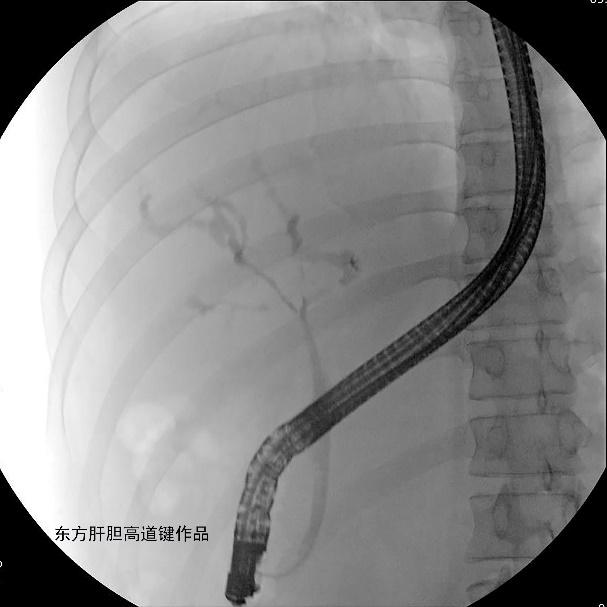

图B

图B:两根导丝分别超选进入右前及左内肝内胆管;左右肝内胆管各抽得白胆汁5ml与15ml,标本送培养;